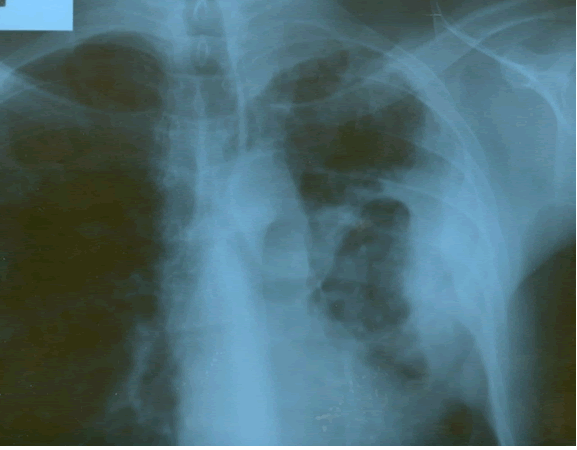

PA and lateral chest film revealed patchy consolidation of the left lung with a large pleural-based mass, left apical pleural thickening, and right upper lobe scarring (Figure 1). Helical CT scan of the chest, abdomen, and pelvis with contrast demonstrates a large, 10.8 x 4.1 cm left pleural-based mass extending into the chest wall and left breast (Figure 2). There was periosteal thickening and irregularity of adjacent ribs. Multiple enlarged mediastinal, left hilar, and supraclavicular nodes were noted, the largest 1.5 x 2.6 cm in the AP window or station five region. There was patchy consolidation of the left and right upper lobes. An MRI of the thorax with contrast was obtained and confirmed the presence of left supraclavicular adenopathy and an enhancing mass with extension into the chest wall involving the ribs, infiltration of the pectoralis muscle, and extension into the left lung parenchyma. The main differential diagnoses at this time were neoplasm (sarcoma, advanced lung cancer, mesothelioma, lymphoma, osteosarcoma).